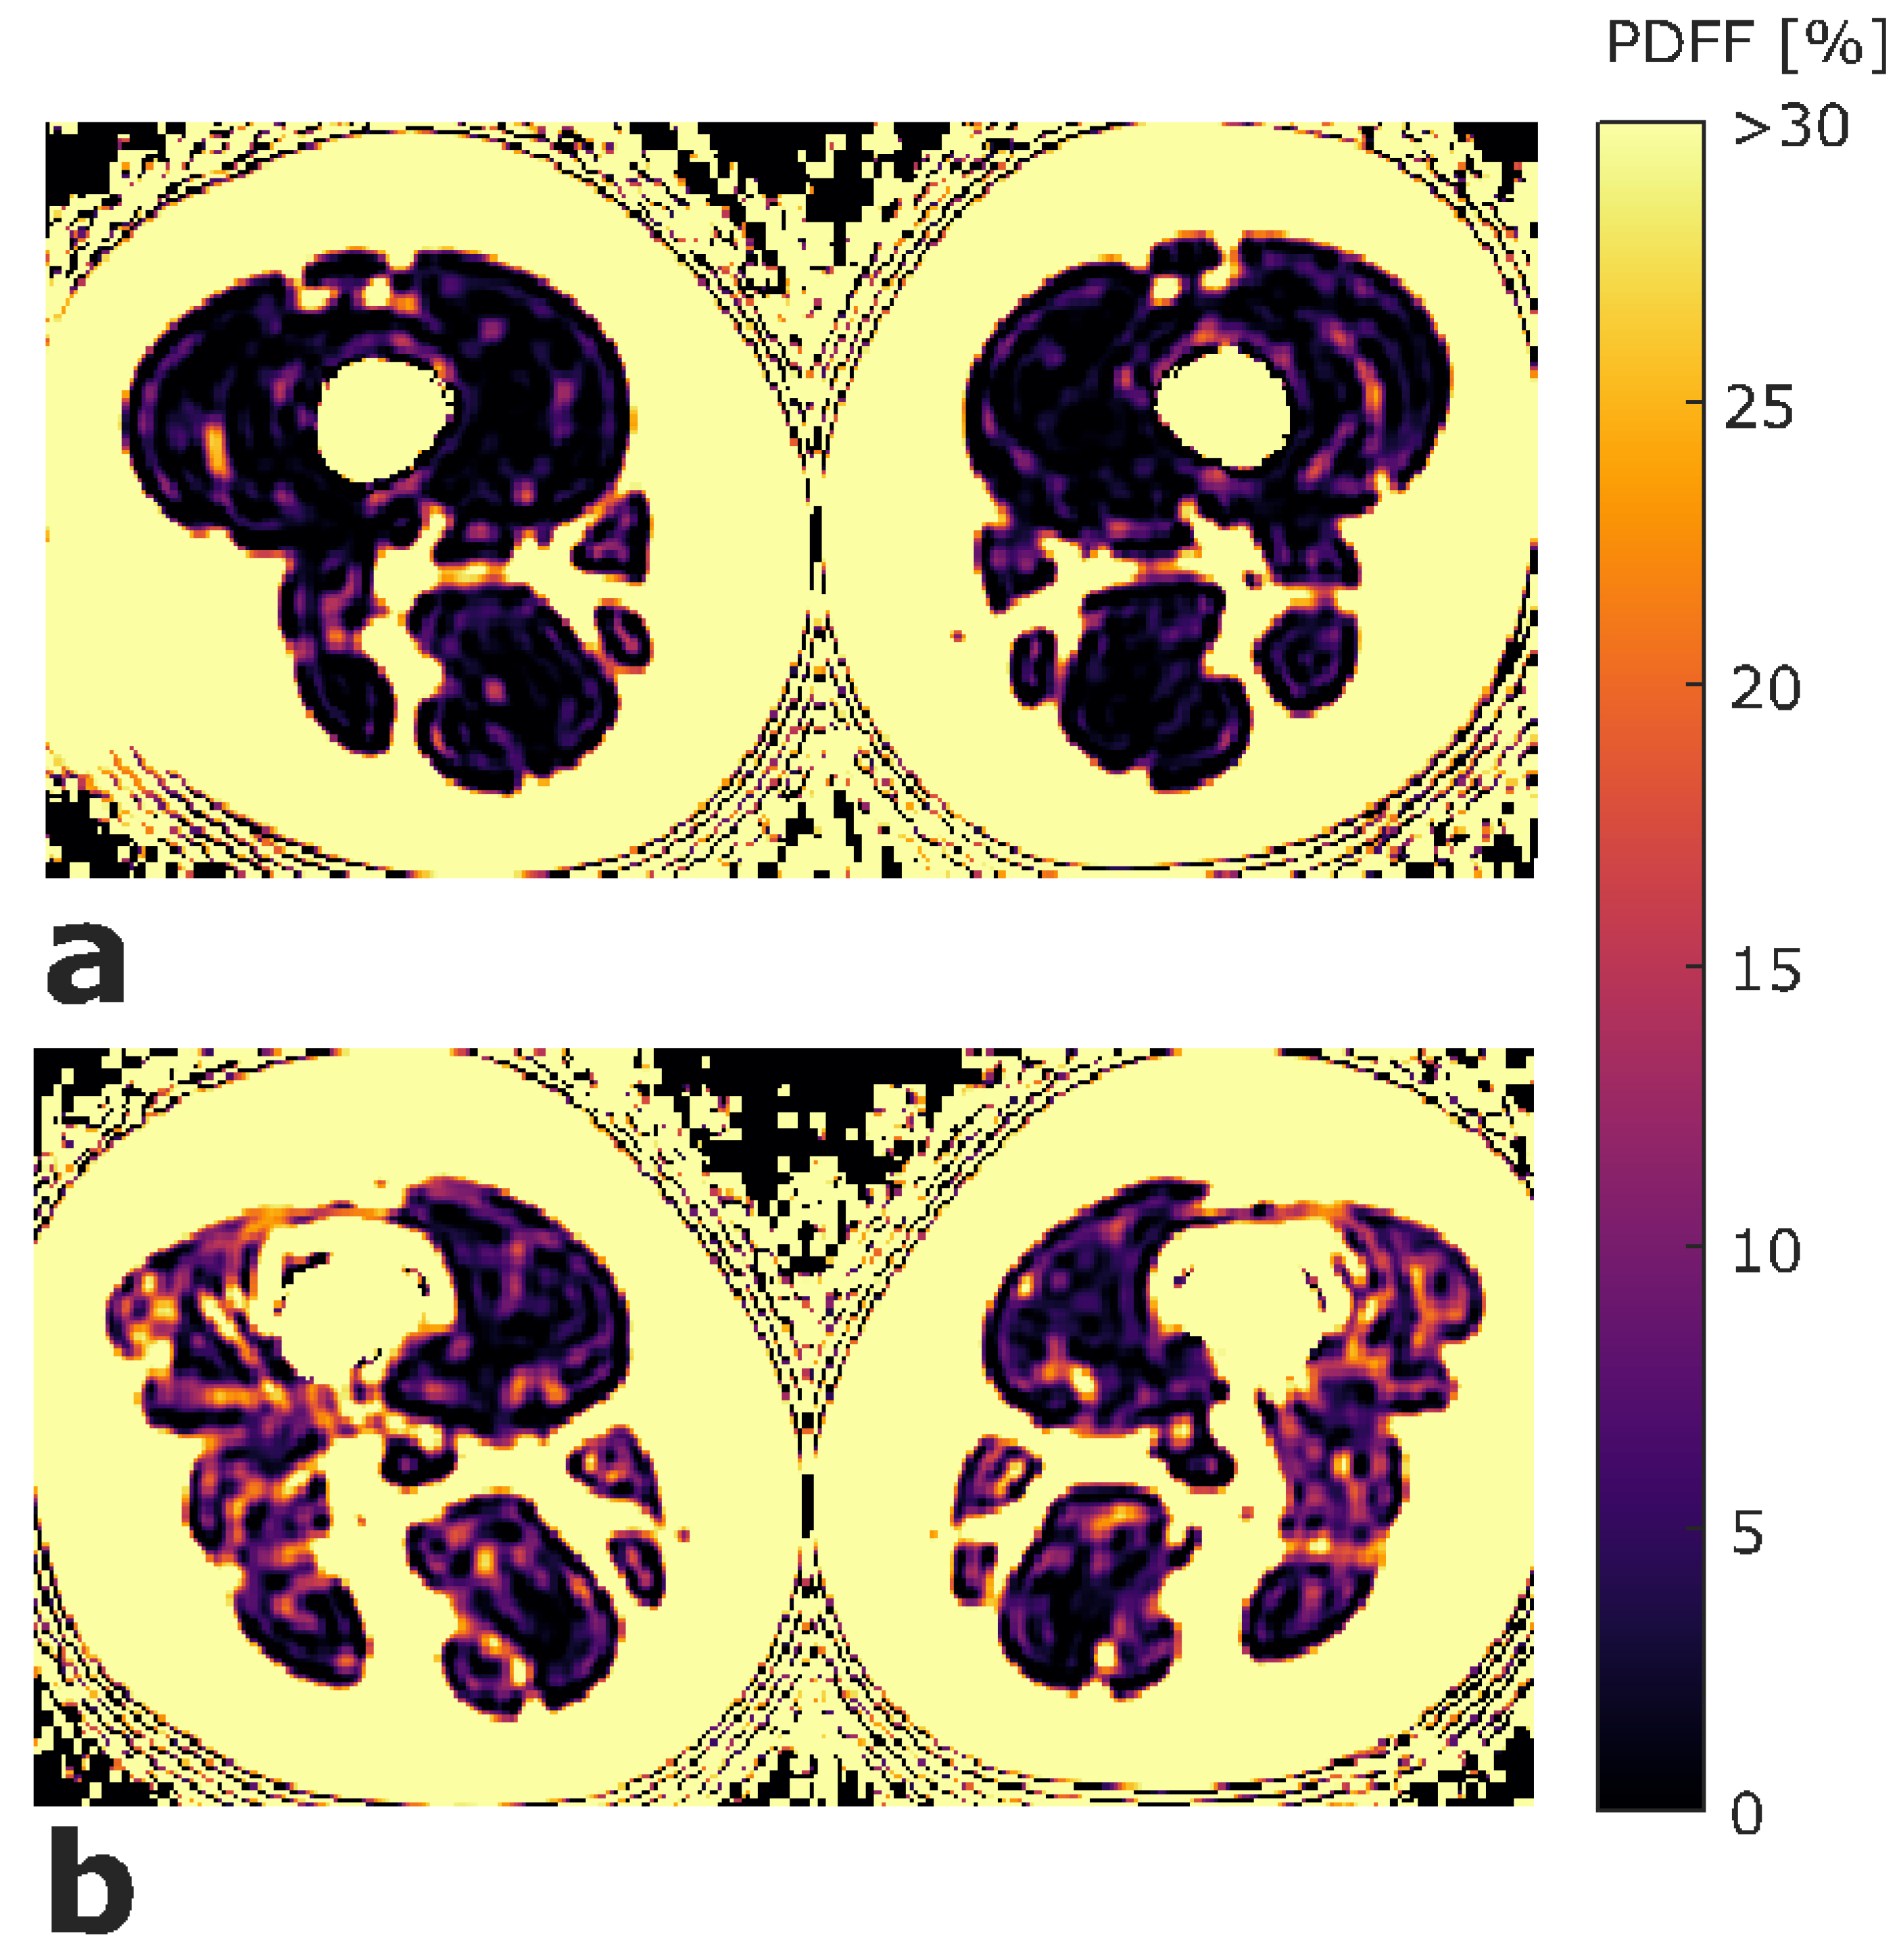

2.4. Texture Analysis of PDFF Maps